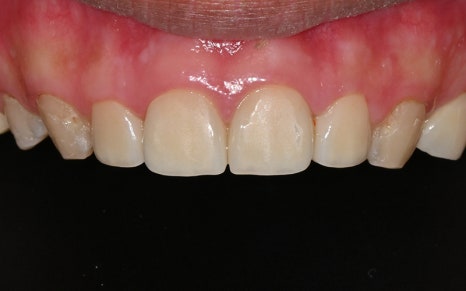

💛 앞니 심미 복원 💛

어느정도 치료를 진행한 후의 모습인데요.

무엇보다도 눈에 띄는 변화는

앞니의 심미 복원입니다.

하지만 치료 후 사진은

완전히 다른 사람이 된 듯한 변화가 느껴집니다.

마치 원래부터 예쁘고 반듯했던 치아처럼,

색상도 자연스럽고

모양도 얼굴형에 딱 맞게 복원되었습니다.

실제로 환자분께서는

“이게 진짜 원래 내 치아 같고,

치료한 티가 하나도 안 난다”며

만족을 표현해주셨고,

“예전에는 항상 소극적이었는데,

요즘은 사람들 앞에서 활짝 웃게 된다”고

말씀해주셨답니다.

저희가 추구하는 ‘자연스러움 속의 심미성’을

가장 잘 보여주는 결과였습니다.

💛 전 > 후 💛

2025.01.05

▼▼▼▼▼

2025.05.21